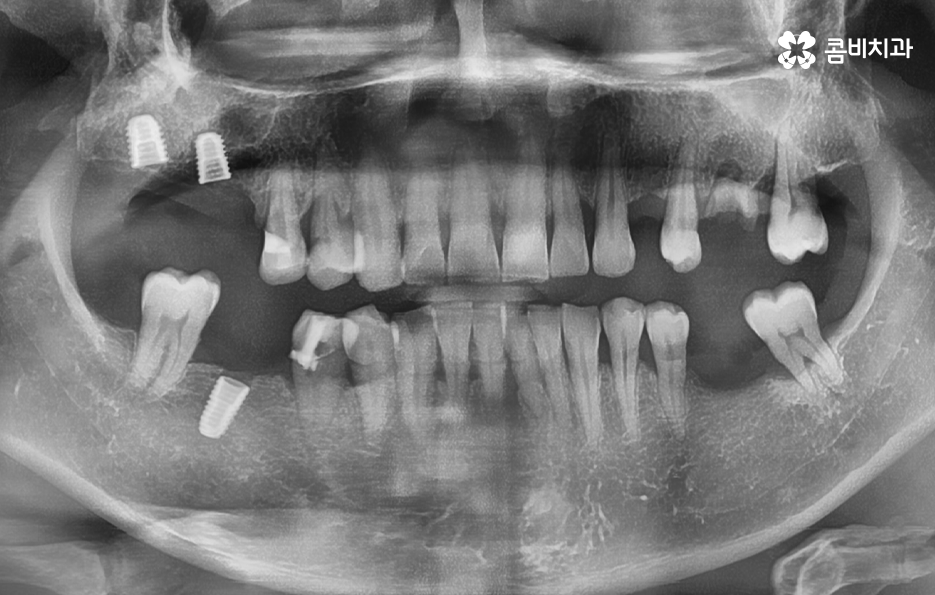

위 사진을 보시면 치아 자체의 노화나 균열도 물론 크지만 잇몸이 내려앉아서 치아의 뿌리 부분이 외부에 노출되어 있는 것을 알 수 있는데요. 노인임플란트 필요로 하는 분들의 치아 상실의 대표적 원인은 충치 부터 오래된 크라운, 치아의 손상 및 균열로 인한 문제도 크겠지만 결정적으로는 치주염으로 인해 잇몸 뼈가 녹고 잇몸 퇴축으로 인한 치아 상실이 노년기에 발생하는 치아 상실의 대표적 원인이 되고 있어요

위 케이스의 노인임플란트 치료의 경우 치아의 균열부터 뿌리까지 깊어진 충치, 치주염 까지 복합적인 이유로 치아를 상실하고 여러 개의 임플란트를 식립한 사례라고 할 수 있는데요. 그래도 아직은 잔존하고 있는 치아가 많기 때문에 이미 상실한 치아에는 노인임플란트 각 위치에 맞게 적절한 치료를 받고 나머지의 자연치아에 대해서는 잘 관리하는 것이 중요한 시점이라 할 수 있어요